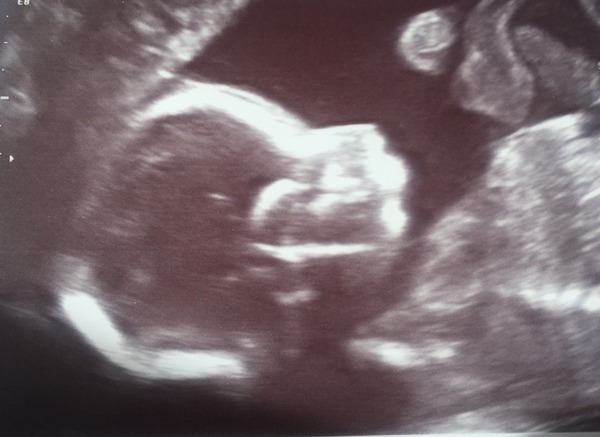

Congrats on scans ladies - it's the backbone 'zipper' that always fascinates me..so clear on the scans!

Lovely scan photos also ladies very clearSmile

Anomaly scan went well, managed to get all the measurements after 45 minutes and me jumping up and down. Actually in a bit of pain from the scan but I don't mind because she was lovely. And. ... team blue!

Finally I had my week 20 scan today and our little girl looks perfect. I am very relieved and totally in love with her already Smile